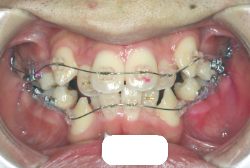

「歯並びの凸凹を直したい」という主訴で来院したケースです。診断の結果、たしかに「叢生」という隙間が足りないと言うことが原因の凸凹症例でした。

しかし、それ以上に問題なのは「前歯の噛み合い方が深すぎる」という症状で、初診の歯の正面写真を見ると下の前歯が全く見えません。こういう症状を矯正学では「過蓋咬合(かがいこうごう)」と言います。過蓋咬合を放置すると、将来的に顎関節に悪影響を与えるとされており、顎関節症の原因因子の一つです。また下の前歯の先端が、上の前歯の裏側の歯茎と強く接触するため、歯周病の原因にもなります。

検査の結果、凸凹が軽症なため非抜歯で矯正すること可能と判断、マルチブラケット装置にて治療しました。治療後は歯並びが綺麗になっただけでなく、噛み合わせ的にも正しい状態が確立しています。